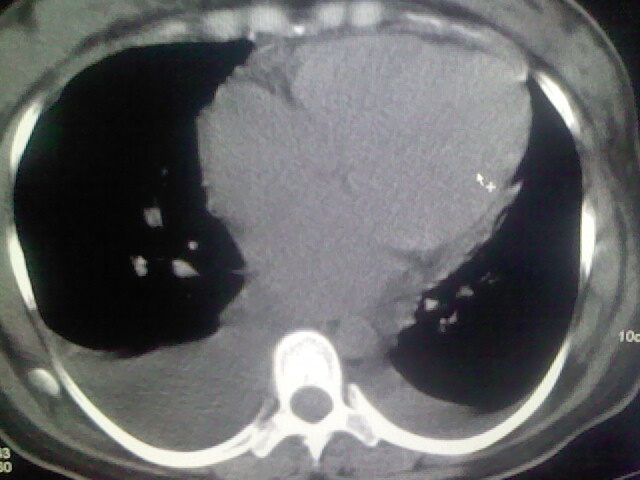

女,24,剖腹产后,突觉胸痛,干咳,不能平卧

全心衰导致积液、肺水肿。不知手术前有无心脏病变?

临床资料及影象表现支持围产期扩张型心肌病改变,心衰。

考虑产后心肌病,心功能不全,肺水肿,双侧胸腔积液。

考虑产后心肌病,心功能不全,肺水肿,双侧胸腔积液。不排除羊水栓塞可能。